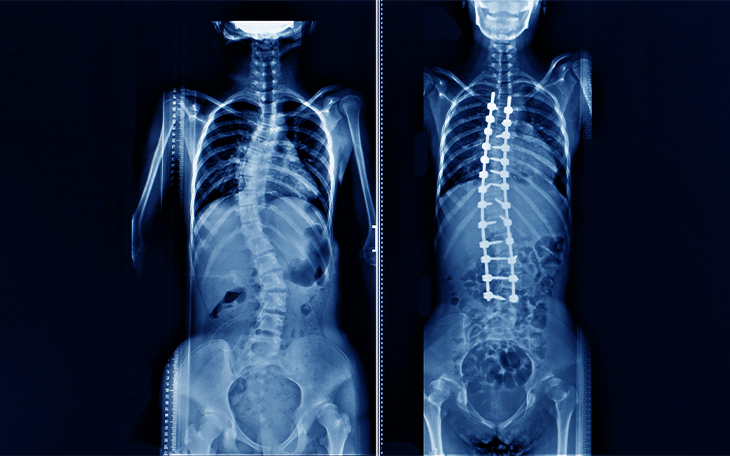

Der Begriff Skoliose bezeichnet eine S-förmige oder C-förmige Verkrümmung der Wirbelsäule in der Frontalebene (sichtbar bei Betrachtung von vorne). Kyphose beschreibt eine verstärkte Vorwärtskrümmung der Wirbelsäule in der Sagittalebene (sichtbar bei Betrachtung von der Seite).

Die wichtigste Untersuchung ist das Röntgenbild in stehender Position, sowohl frontal (AP) als auch seitlich (lateral).

Operative Therapie

Die operative Versorgung besteht in der Regel aus einer Wirbelsäulenversteifung (Spinalfusion) unter Einsatz von Schrauben und Stäben. Diese wird notwendig, wenn eine relevante Fehlstellung oder Instabilität vorliegt.

Eine erfolgreiche OP setzt eine gute Korrektur in der Frontal- und Sagittalebene voraus. Studien zeigen, dass über 90 % der Patienten mit dem Ergebnis ihrer Operation zufrieden sind. Zwar treten bei Erwachsenen häufiger Komplikationen auf als bei Kindern, diese sind jedoch meist beherrschbar und beeinflussen das Endergebnis kaum.

Überblick

Skoliose bezeichnet eine S- oder C-förmige Verkrümmung der Wirbelsäule in der Frontalebene (von vorn betrachtet). Zusätzlich zur Verkrümmung kommt es häufig auch zu einer Rotation der Wirbelsäule, bei der Rippen und Rumpf rotieren. Dies führt zu einem sichtbaren Rippenbuckel oder einer seitlichen Vorwölbung des Rückens.

Häufige körperliche Befunde sind sichtbare Deformitäten der Wirbelsäule, ein Rippenbuckel und ein Rumpfversatz. Die Beweglichkeit der Lendenwirbelsäule ist meist erhalten, neurologische Ausfälle selten.

Diagnostik

Behandlung

Das chirurgische Standardverfahren ist die dorsale (hintere) Wirbelsäulenversteifung mit Implantaten und autologem (eigenem) Knochentransplantat.

Bildquelle: www.docset.de